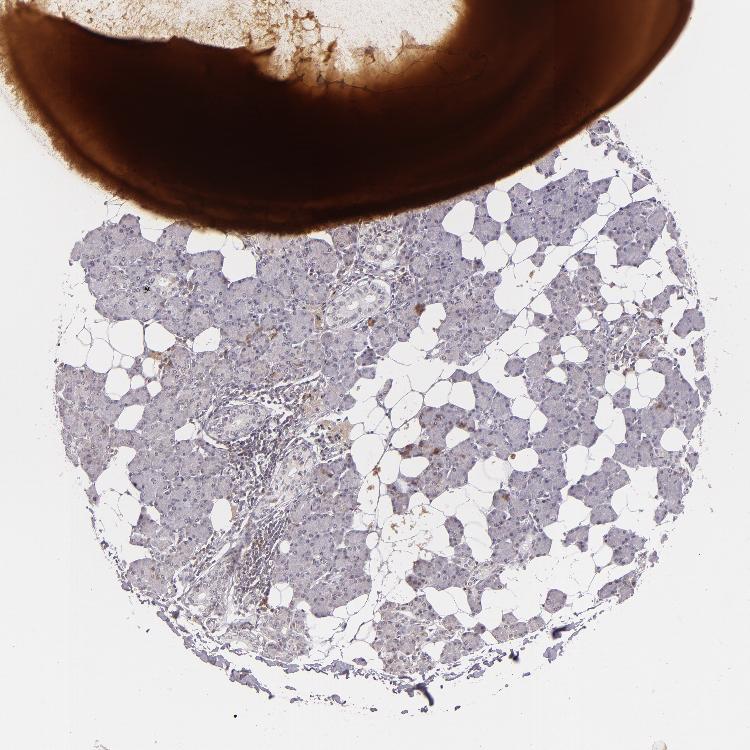

SALIVARY GLAND - Antibody stainingi

Antibody staining in the annotated cell types in the current human tissue is reported as not detected, low, medium, or high, based on conventional immunohistochemistry profiling in selected tissues. This score is based on the combination of the staining intensity and fraction of stained cells.

Each image is clickable and will lead to virtual microscopy that enables deeper exploration of all samples and also displays staining intensity scores, fraction scores and subcellular localization as well as patient and tissue information for each sample.

Antibody HPA001302Antibody HPA005688Antibody CAB002047

Glandular cells MediumHighLow